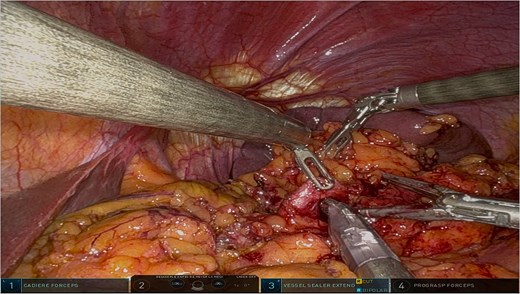

The surgery was performed using the Da Vinci robotic system under general anesthesia. The patient was positioned supine with reverse Trendelenburg. Four robotic trocars and one assistant trocar were placed. The gastro-splenic ligament was dissected to expose the distal pancreas, and the pancreas was transected using a linear stapler, ensuring tumor-free margins (Fig. 2). The splenic artery and vein were individually ligated with robotic sutures, and the spleen was mobilized and removed along with the pancreas (Fig. 3). The specimen was extracted via mini-laparotomy and sent for histopathological analysis (Fig. 4).

Intraoperative view showcasing the dissection and mobilization of the greater curvature of the stomach. This involved dividing the gastrocolic ligament to expose the retroperitoneal space, providing access to the distal pancreas while preserving surrounding structures to minimize surgical trauma.